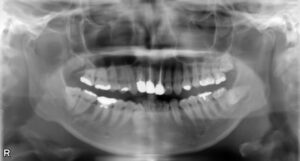

• 下顎大臼歯3本欠損症例

BEFORE AFTER 60歳男性/下3本欠損/インプラント埋込手術 【治療内容】 左下第一大臼歯は他院で治療中でした…